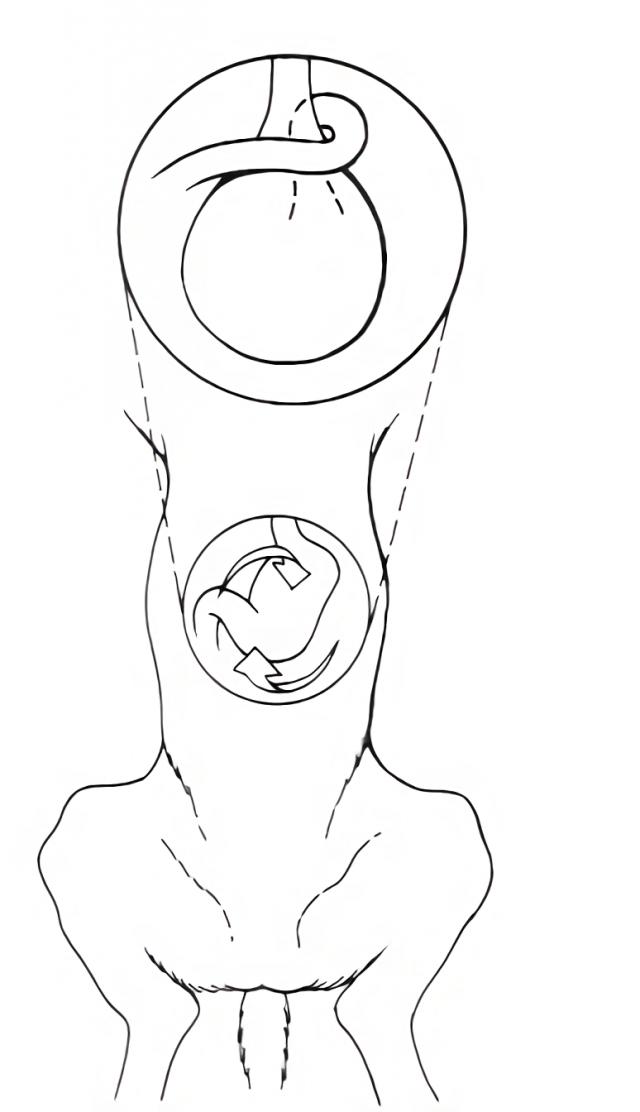

犬胃扭转示意图 |

资源描述:食管末端的胃沿顺时针方向可旋转90°~360°,这种旋转使幽门偏向中线的左侧,使十二指肠进入食管末端和胃之间。

文件来源:网络

从后向前方看,在食管末端的胃沿顺时针方向可旋转90°~360°,这种旋转使幽门偏向中线的左侧,使十二指肠进入食管末端和胃之间。根据不同的扭转程度,脾脏可能在不同的位置从腹腔左前部到达后部。当胃扭转大于180°时,会使贲门闭塞。